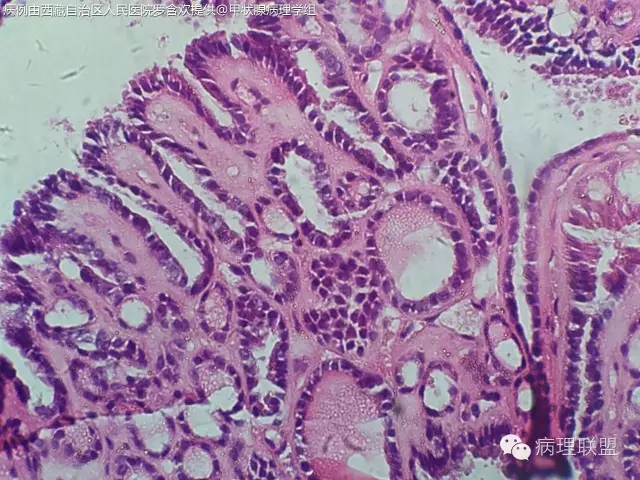

请教老师们一个病例,女,61岁,双侧甲状腺占位。(病例由西藏自治区人民医院 罗含欢 提供,致谢!)

没有看到浸润性生长,仔细看细胞核是否有乳头状癌的特征(核沟、毛玻璃样、加包涵体),图片不是很清楚,目前看上去应该是良性的,没有间质反应和砂粒体。浅见。

核不清,宽厚纤维间质,核重叠,应为乳头状癌

@罗含欢 结节性甲状腺肿伴出血囊性变,部分滤泡上皮乳头状增生

结甲,部分腺上皮乳头状增生

@罗含欢 @周泉 @邓永键 @韩绘宇 这例请几位老师看一下

@毕超 上一例跟你这个不一样。诊断结节性甲状腺肿伴滤泡上皮乳头状增生就可以了。唯一有点怀疑的是那小小灶真的乳头状结构的区域,虽然不是很清楚,但是可以隐约看出其细胞排列相当的整齐,规则。跟你这例完全不一样,核也是位于同一水平,个人看法,不对的地方请老师们指正

第一例乳头内有滤泡,第二例是真正纤维轴心,两例乳头不一样